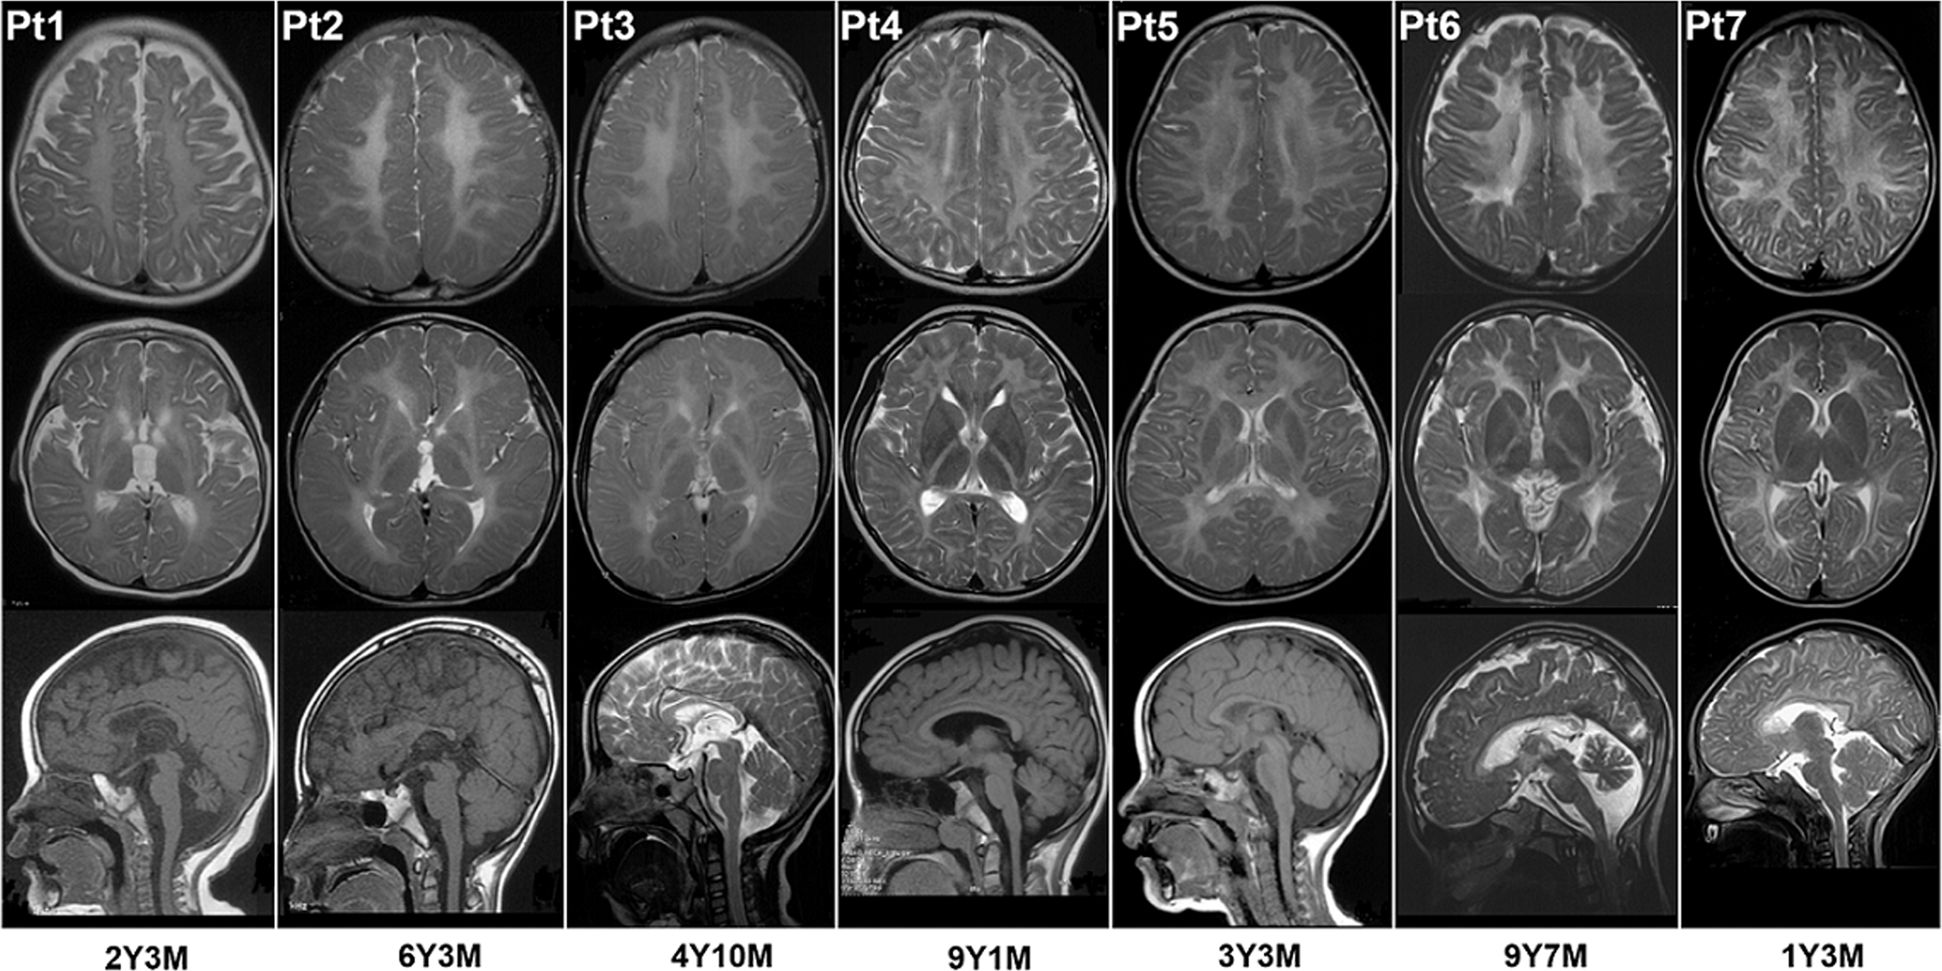

Fig. 3

MRI images of seven patients. Row 1 and row 2 are axial T2-weighted images, showing diffuse hypomyelination in cerebral white matter in all seven patients and atrophy of the basal ganglia in Pt1, Pt2, and Pt3. Pt1 also demonstrated an abnormal signal in the putamen and caudate nucleus. Raw 3 are midsagittal T1-weighted or T2-weighted images, showing atrophy of cerebellum in Pt1 and Pt6. Six patients were diagnosed with HLD6 (Pt1, Pt2, Pt3), HLD7 (Pt4), HLD11 (Pt5, Pt6), and SOX10 related disorder (Pt7), respectively. Y years, M months